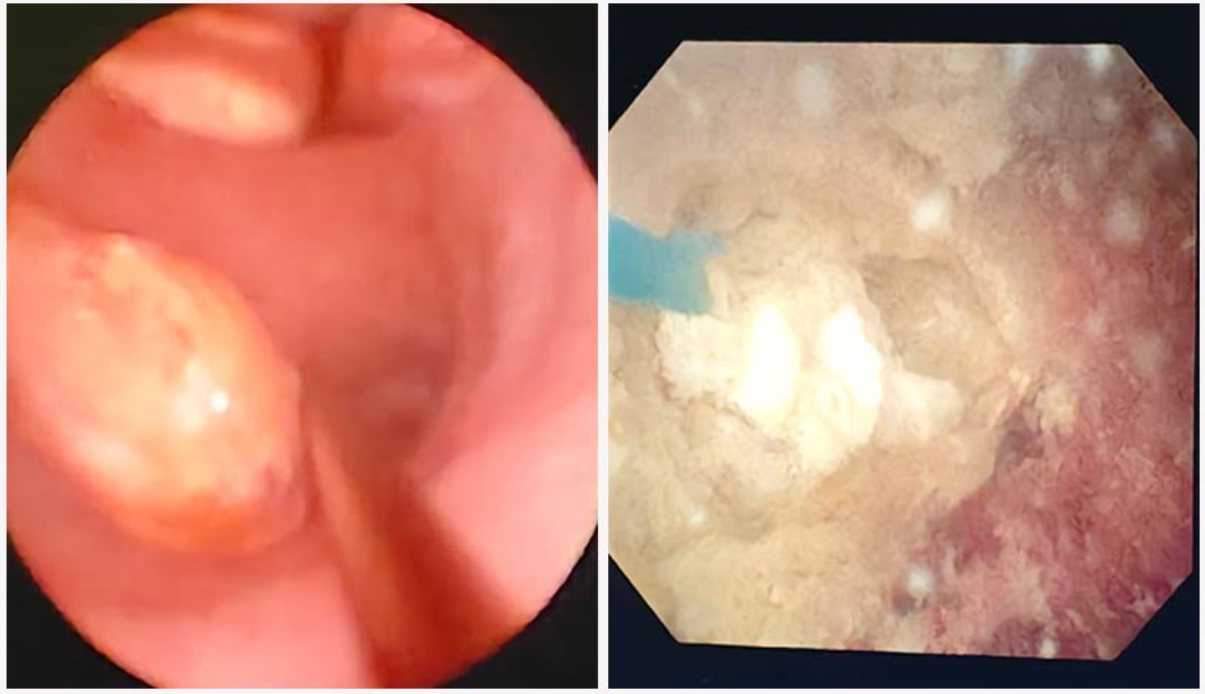

73的姜大爷(化名),因基础疾病较多在我院老年科住院治疗。最近,医护人员发现姜大爷尿液时有带血,专科会诊后怀疑有尿路结石的可能。

包皮环切术,睾丸鞘膜积液切除术,经尿道前列腺等离子电切,膀胱肿瘤电切术,肾输尿管膀胱结石的钬激光碎石,肾囊肿的微创治疗等。